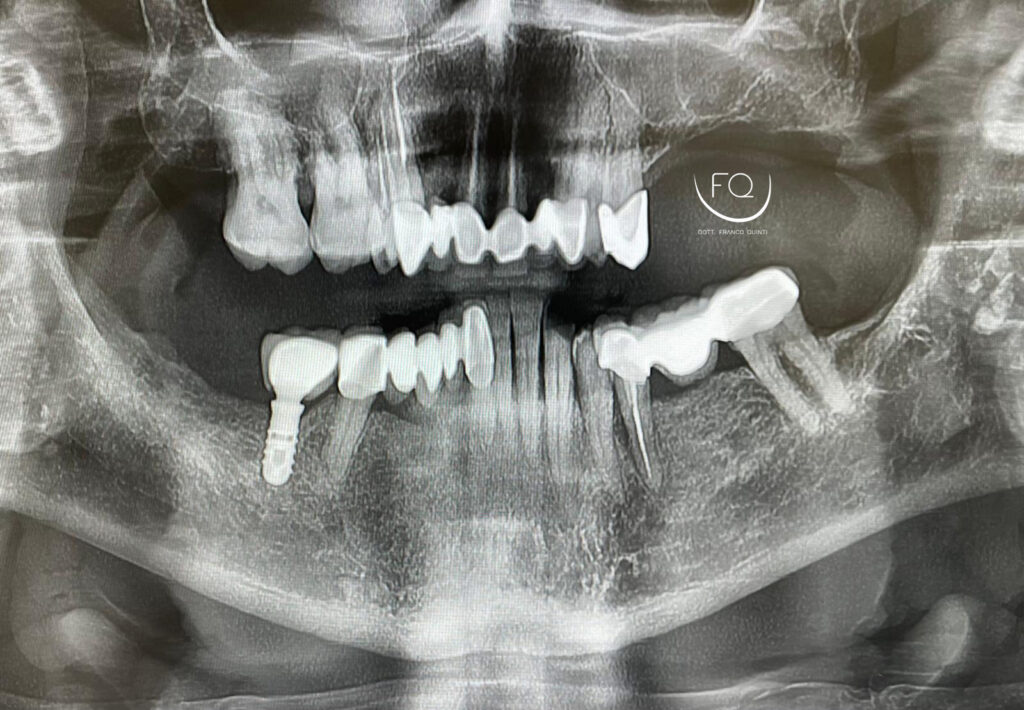

Dall’immagine iniziale è possibile apprezzare l’estrusione del gruppo incisivo inferiore il quale è stato corretta con la protesi provvisoria a carico immediato stampata in 3D.